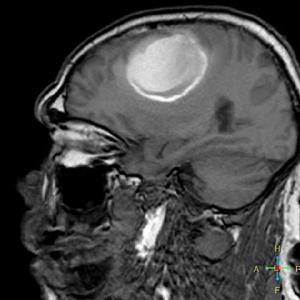

顱內刺激就是指對腦內進行直接刺激,主要可分為兩種,第一種為有創顱內刺激,如:插入式電極,電極放電刺激大腦神經元;第二種為無創顱內刺激,如:經顱磁刺激(Transcranial Magnetic Stimulation ,TMS),是一種利用脈衝磁場作用於中樞神經系統(主要是大腦),改變皮層神經細胞的膜電位,使之產生感應電流,影響腦內代謝和神經電活動,從而引起一系列生理生化反應的磁刺激技術。

治療癲癇:可以經顱內電極植入明確致癇灶後,均行皮層電刺激定位功能區,根據致癇灶與功能區關係圖決定治療方案。